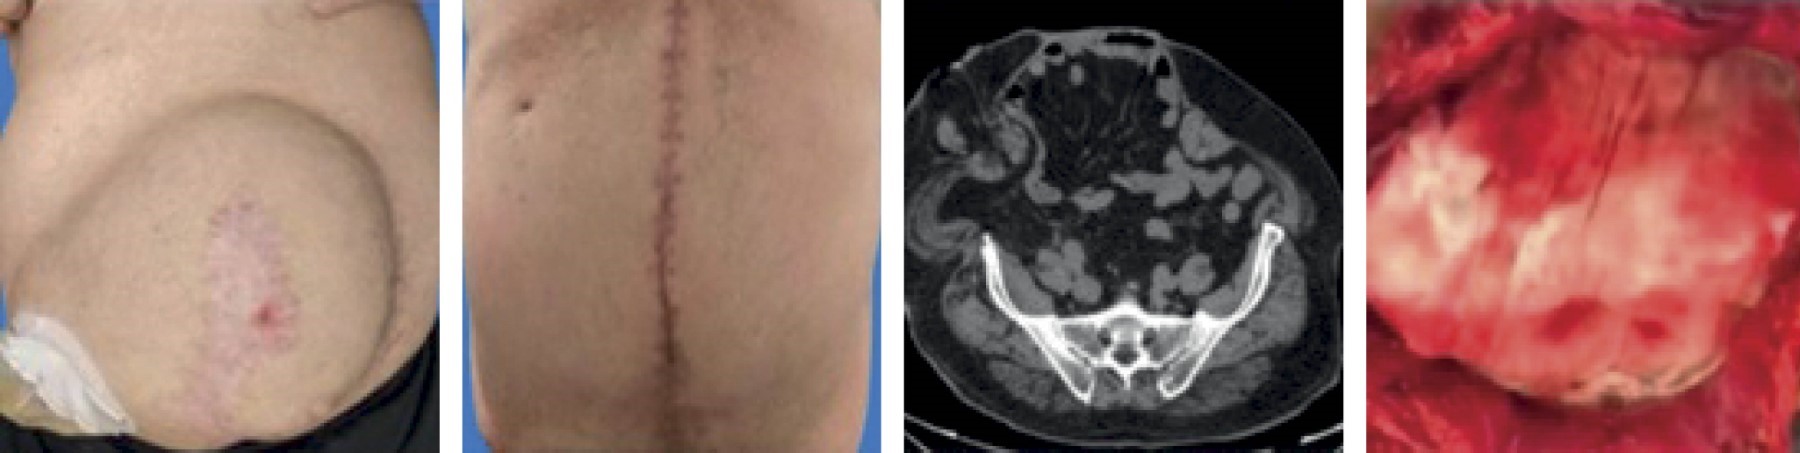

Caso 1. Hombre de 45 años, con antecedentes crónico degenerativos negados; antecedentes quirúrgicos positivos para laparotomía exploradora cuatro años previos. Inició padecimiento actual un año antes del evento quirúrgico con aumento de volumen en el sitio de la laparotomía previa, no doloroso, de 40 × 18 cm. Fue protocolizado por el servicio de cirugía general, realizando plastia ventral con separación anatómica de componentes, según la técnica de Carbonell-Bonafé. Requirió protocolo prequirúrgico con neumoperitoneo progresivo + reconexión de tránsito intestinal. Inició la vía oral tres días después del evento quirúrgico. Durante el cuarto día postoperatorio se presentó infección de herida quirúrgica, que requirió lavado quirúrgico en tres ocasiones. Egresó al séptimo día postoperatorio sin complicaciones posteriores a su egreso (Figura 1).

Figura 1